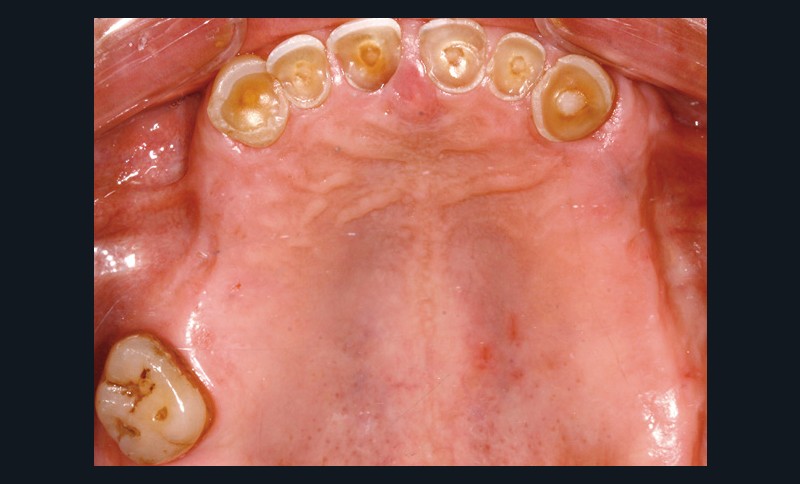

• L’examen intrabuccal montre de nombreux édentements non compensés (14, 15, 16, 24, 25, 26, 27, 47 et 36) ainsi que des pertes de substance très importantes, notamment dans le secteur antérieur.

Une attrition sévère, couplée à une occlusion sans calage postérieur, a engendré des difficultés pour s’alimenter.

La perte de dimension verticale par usure prématurée nécessite d’augmenter cette dernière de façon importante, et en une seule fois.

– perte de substance extrême du bloc incisivo-canin maxillaire et des incisives mandibulaires ;